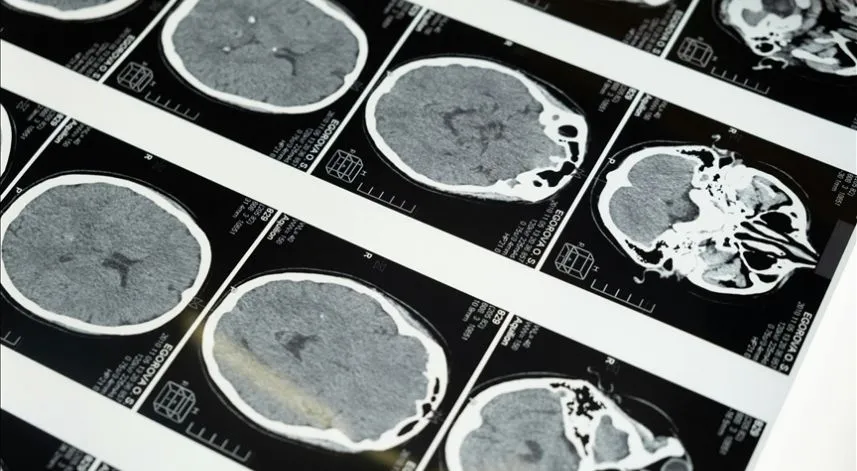

Hastaneden yapılan açıklamada görüşlerine yer verilen Asil, dünyada en sık görülen üçüncü ölüm nedeni olan inmenin, yüzde ani kayma, kol veya bacakta güçsüzlük ve konuşma bozukluğu gibi belirtilerle ortaya çıkabileceğini belirtti.

Bu semptomların görülmesi halinde zaman kaybedilmemesi gerektiğine dikkat çeken Asil, "İnme, ülkemizde ve dünyada önemli bir ölüm ve sakatlık nedeni." açıklamasını yaptı.

Diyabet, hipertansiyon, obezite, yüksek kolesterol ve kalp hastalarının inme açısından riskli grupta olduğunu vurgulayan Asil, "Erken müdahale, felcin kalıcı hasar bırakmasını önleyebilir." değerlendirmesini yaptı.

"Damar tıkanıklığına bağlı iskemik inme, erken dönemde tedavi edilebilen bir hastalık haline geldi. Beyinde tıkanan damarlar ilaçlar ve anjiyografik yöntemlerle açılabiliyor, böylece hastanın şikayetleri kısmen ya da tamamen düzelebiliyor. Tedavide en kritik unsur zamanında müdahale."